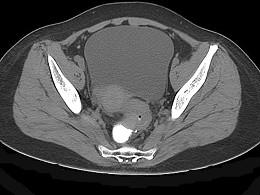

问题 男,67岁,排便习惯改变,血便三个月入院,CT检查如图所示,下列说法错误的是 ( )

选项 A、此为直肠息肉 B、此为直肠癌 C、其表面欠光整,边界欠清晰 D、可做直肠指检及活检以确定病变性质 E、直肠肠腔局限性增厚

答案 A